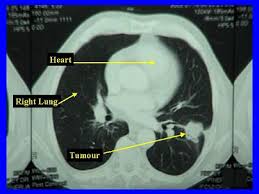

Lung Cancer Symptoms Australia / Lung Cancer Awareness Month Connect Ability Australia - People with lung cancer often experience signs and symptoms of the cancer, as well as side effects of treatment.. Stage 4a lung cancer, in which cancer has spread within the chest to the opposite lung; Persistent cough or a new or changed wheeze (or both) It is the fifth most common cancer in australia, accounting for 9% of all cancers diagnosed. People with lung cancer often experience signs and symptoms of the cancer, as well as side effects of treatment. It is generally recognised that early diagnosis of lung cancer could be an important factor in improving both the survival rate and patients' quality of life.

Some of the most common are horner's syndrome, superior vena cava syndrome, and paraneoplastic syndrome. Lung cancer signs and symptoms can be difficult to detect, and is often discovered when it is more advanced. A person diagnosed with lung cancer may also have symptoms such as fatigue, weight loss, hoarse voice, wheezing, difficulty swallowing, abdominal or joint pain, and enlarged fingertips (finger clubbing). Sores or ulcers that don't heal. A number of studies have identified certain symptoms to be more prevalent at various stages of the disease development.

November Lung Cancer Awareness Month Edmonton Family Medical Centre from edmontonfmc.com.au A number of studies have identified certain symptoms to be more prevalent at various stages of the disease development. Cancer australia was established by the australian government in 2006 to benefit all australians affected by cancer, and their families and carers. Changes to the voice such as hoarseness. Chronic, hacking, raspy coughing, sometimes with mucus that has blood in it; Symptoms of lung cancer at stage 4. It is generally recognised that early diagnosis of lung cancer could be an important factor in improving both the survival rate and patients' quality of life. Lung cancer has the lowest survival rate of all cancers in adults, with only 13% of affected individuals in australia surviving for five or more years following a diagnosis. Most factors include the patient's outlook, treatment plan and overall health.

A person diagnosed with lung cancer may also have experienced symptoms such as fatigue, weight loss, hoarse voice, wheezing, difficulty swallowing, abdominal or joint pain, and enlarged fingertips (finger clubbing). Some of the most common are horner's syndrome, superior vena cava syndrome, and paraneoplastic syndrome. Or to the fluid around the lungs or heart (malignant effusion); Symptoms include trouble breathing, chest pain, cough, wheezing, vocal changes, unexplained weight loss, bone pain and. Lung cancer signs and symptoms. The latter degree of the disease is very poorly tolerated by patients. Most factors include the patient's outlook, treatment plan and overall health. People with lung cancer often experience signs and symptoms of the cancer, as well as side effects of treatment. Feeling there is something stuck in the throat. Persistent cough or a new or changed wheeze (or both) A number of studies have identified certain symptoms to be more prevalent at various stages of the disease development. In australia, lung cancer is the fifth most common cancer. Stage 4c lung cancer, in which cancer has spread to one or multiple.

Lung Cancer Overview Cancer Council Victoria from www.cancervic.org.au Stage 4a lung cancer, in which cancer has spread within the chest to the opposite lung; When signs of the disease start to appear, they can include: People with lung cancer often experience signs and symptoms of the cancer, as well as side effects of treatment. A symptom is a feeling, such as fatigue or loss of appetite. Lung cancer usually has no symptoms in its early stages. Chronic, hacking, raspy coughing, sometimes with mucus that has blood in it; Having any one of these symptoms does not necessarily mean that you have lung cancer. Symptoms of this disease may be referred to as pancoast syndrome and include pain in the shoulder, inner side of the arm, and hand.

Stay up to date with the latest information, news, services and events by signing up to our database. While community awareness of the link between smoking and lung cancer in australia is high 18 , awareness of lung cancer symptom recognition is unknown. Each year, about 12,200 australians are diagnosed with lung cancer. If you have a moist cough, your mucus should be clear or white in colour. There can be many different reasons for having a persistent cough; Pancoast tumors rarely produce symptoms related to the lungs themselves, such as chest pain or cough. Lung cancer is the fifth most common cancer in australia and accounts for 9% of all cancers. A number of studies have identified certain symptoms to be more prevalent at various stages of the disease development. Lung cancer signs and symptoms can be difficult to detect, and is often discovered when it is more advanced. A person diagnosed with lung cancer may also have symptoms such as fatigue, weight loss, hoarse voice, wheezing, difficulty swallowing, abdominal or joint pain, and enlarged fingertips (finger clubbing). Lung cancer is the fifth most common cancer australia with over 11,000 people diagnosed in 2012. Stage 4c lung cancer, in which cancer has spread to one or multiple. If it spreads you might develop other symptoms like nausea, headaches and pain in other parts of your body.